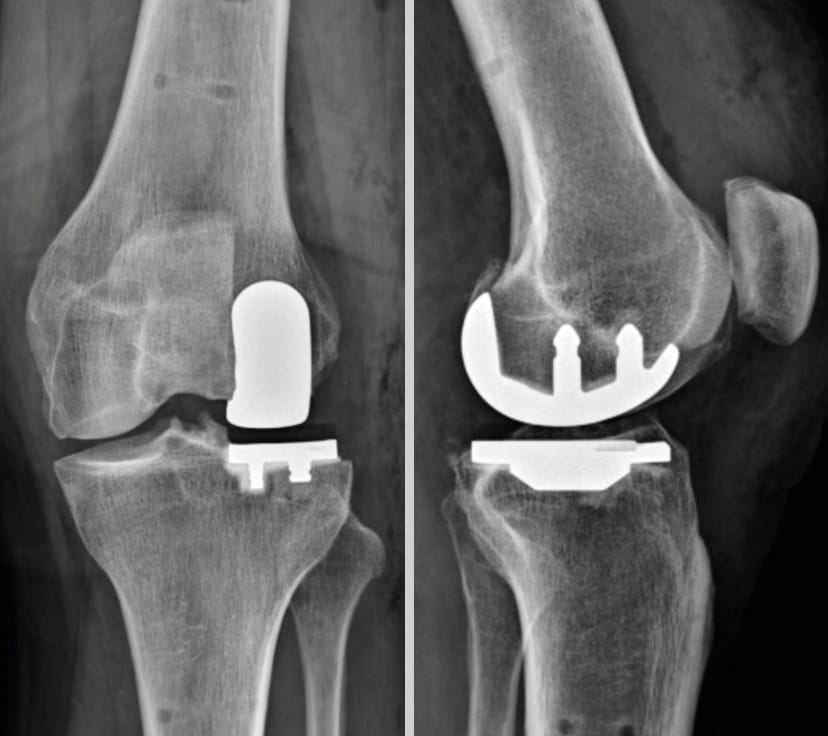

Our article focuses exclusively on unicompartmental knee arthroplasty (UKA), particularly the implantation of the Sigma™ Partial Knee prosthesis, a cemented, resurfacing-type prosthesis, suitable for the management of medial (Figure 1) or lateral (Figure 2) femorotibial osteoarthritis.